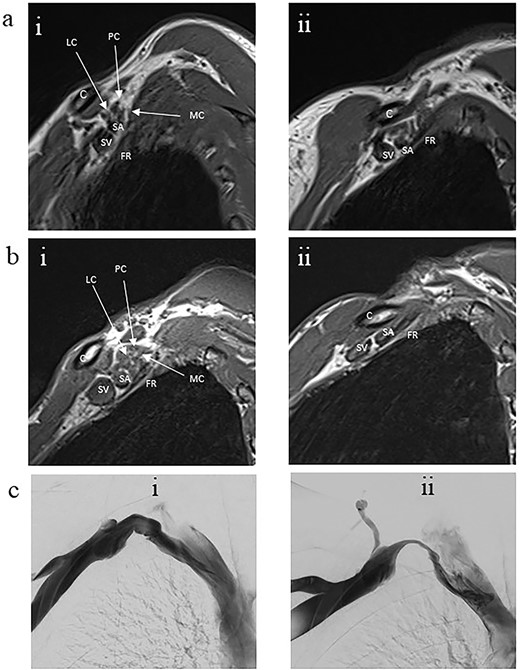

With the arm elevated, there is narrowing of the costoclavicular space between the posterior border of the clavicle and anterior border of the first rib (Figs 1 and 3). In unaffected patients, there is a small amount of fat that persists around the cords of the brachial plexus with the arm elevated (Fig. 2). In our series, we considered a patient to be positive for nTOS if there is loss of the perineural fat signal demonstrating that the nerves are in direct contact with the posterior border of the clavicle and anterior border of the first rib (Fig. 1b).

Panel a. Sagittal T1-weighted MRI of the costoclavicular space without imaging evidence of nTOS. Arm alongside the body (i) and arm elevated (ii). Maintenance of a fat plane surrounding the cords is seen with physiological narrowing of the space. Panel b. Sagittal T1-weighted MRI of the costoclavicular space with imaging evidence of nTOS. Arm alongside the body (i) and arm elevated (ii). Narrowing of the costoclavicular space and complete effacement of the fat indicating brachial plexus compression. Panel c. Venograms conducted with contrast injection in the antecubital vein while the arm is alongside (i) and in salute pose (ii) demonstrates tight stenosis of the subclavian vein and collateral flow. The MRI also showed effacement of the brachial plexus. The 36 year-old male subject had an excellent outcome after excision of the 1st rib. C: Clavicle; FR: First rib, SV: Subclavian vein, SA: Subclavian artery, LC: Lateral cord, MC: Medial cord, PC: Posterior cord.